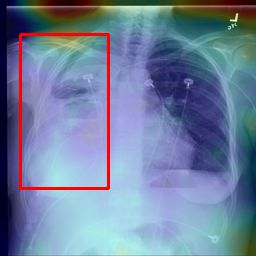

Deployments of artificial intelligence in medical diagnostics mandate not just accuracy and efficacy but also trust, emphasizing the need for explainability in machine decisions. The recent trend in automated medical image diagnostics leans towards the deployment of Transformer-based architectures, credited to their impressive capabilities. Since the self-attention feature of transformers contributes towards identifying crucial regions during the classification process, they enhance the trustability of the methods. However, the complex intricacies of these attention mechanisms may fall short of effectively pinpointing the regions of interest directly influencing AI decisions. Our research endeavors to innovate a unique attention block that underscores the correlation between 'regions' rather than 'pixels'. To address this challenge, we introduce an innovative system grounded in prototype learning, featuring an advanced self-attention mechanism that goes beyond conventional ad-hoc visual explanation techniques by offering comprehensible visual insights. A combined quantitative and qualitative methodological approach was used to demonstrate the effectiveness of the proposed method on the large-scale NIH chest X-ray dataset. Experimental results showed that our proposed method offers a promising direction for explainability, which can lead to the development of more trustable systems, which can facilitate easier and rapid adoption of such technology into routine clinics. The code is available at www.github.com/NUBagcilab/r2r_proto.